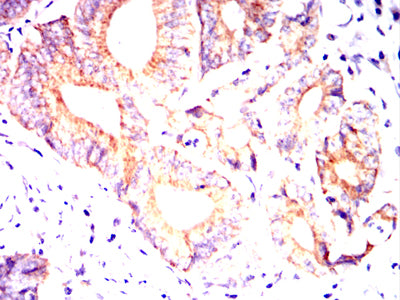

![MUC13 Mouse mAb[63965]](https://img1.dxycdn.com/p/s14/2025/0922/462/2192438545746699691.jpg)

Immunohistochemical analysis of paraffin-embedded human rectal cancer tissues using MUC13 mouse mAb with DAB staining.